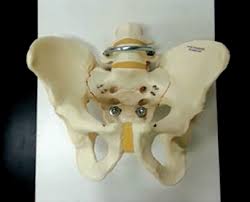

Anterior Superior Iliac Spine, Appendicular Skeleton And Joints Ppt Download : It can be palpated by putting the hands at the top of the hipbones and following the bony margins toward the front of the hips.. The posterior border of the ala, shorter than the anterior, also presents two projections separated by a notch, the posterior superior iliac spine and the posterior inferior iliac spine. Jun 28, 2021 · insertion: Asis, anterior superior iliac spine. Diagnosis is made with pelvis radiographs that shows an avulsion off the aiis. Anterior angulation of the coccyx may be a normal variant but poses a diagnostic challenge for those considering coccygeal trauma.

Classification four types of coccyx have been described: The anterior superior iliac spine is a bony projection of the iliac bone, and an important landmark of surface anatomy. It can be palpated by putting the hands at the top of the hipbones and following the bony margins toward the front of the hips. The blog post articles in this. Jun 09, 2015 · at the posterior end of the ilium, the iliac crest narrows before terminating at another bony process known as the posterior superior iliac spine.

It provides attachment for the inguinal ligament , the sartorius muscle , 1 4 and the tensor fasciae latae muscle. The anterior superior iliac spine (asis) is the most anterior part of the iliac crest. An anterior superior iliac spine (asis) avulsion is a traumatic avulsion of the asis due to a sudden and forceful contraction of the sartorius and tensor fascia lata that occurs in young athletes. Asis, anterior superior iliac spine. This part is the most observable and palpable of the pelvis. The posterior border of the ala, shorter than the anterior, also presents two projections separated by a notch, the posterior superior iliac spine and the posterior inferior iliac spine. Diagnosis is made radiographically with displaced injuries but ct/mri may be required to diagnosis nondisplaced fractures. It provides attachment for the inguinal ligament, and the sartorius muscle. An anterior inferior iliac spine (aiis) avulsion is an apophyseal avulsion injury seen in adolescent athletes as a result of eccentric contraction of the rectus femoris. It refers to the anterior extremity of the iliac crest of the pelvis. The anterior superior iliac spine refers to the anterior extremity of the iliac crest of the pelvis. Outer lip of anterior iliac crest, anterior superior iliac spine (asis) insertion: Classification four types of coccyx have been described: